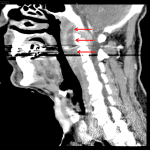

- Large peripherally enhancing retropharyngeal fluid collection extending from the skull base to the level of the C2-C3 disc space. Associated mass effect with partial effacement of the nasopharynx and oropharynx

- Soft tissue thickening and possible thin peripherally enhancing fluid collection along the posterior margin of the C1 and C2 vertebral bodies

Large retropharyngeal abscess measuring 6 by 3 by 5 cm with mass effect on and partial effacement of the nasopharynx and oropharynx. The abscess extends inferiorly to the level of C2-C3 without findings to suggest descending mediastinitis at present.

Soft tissue thickening and possible thin peripherally enhancing fluid collection in the ventral epidural space at the level of C1-C2, which is concerning for epidural abscess. Recommend C spine MRI with and without contrast for further assessment.